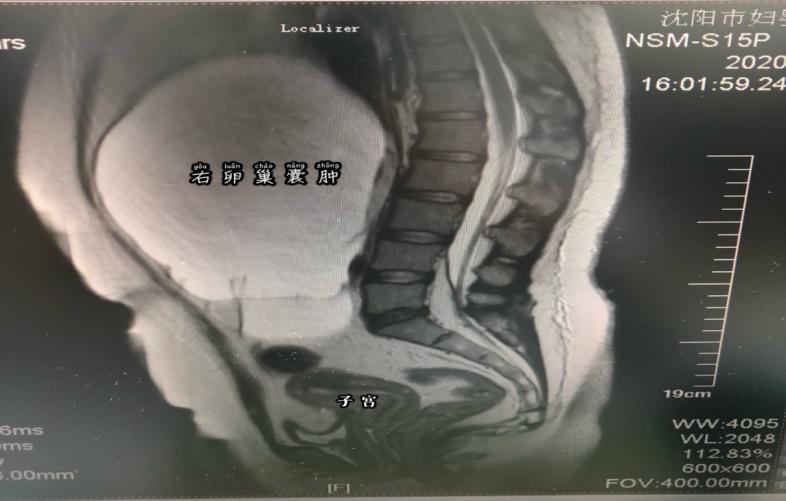

坐在诊室里,被自己肚子里的巨大囊肿吓坏了的孙女士非常忐忑,也十分后悔。其实,在2019年下半年孙女士就发现有点"发福",但因为素来她就比较丰满,以为自己是胖了,也没在意。直到2019年底自己隐约摸到肚子里有个包块,去医院检查才发现是盆腔囊肿。医生当即建议手术治疗,但是因为年底工作繁忙,再加上没有任何症状,也就一拖再拖。结果,因为新冠疫情一直等到2020年5月才来到沈阳市妇婴医院妇科门诊,经过三维彩超及磁共振等检查发现孙女士的囊肿是来源于附件区,最大径线27厘米,已经占据了几乎整个腹腔,手术治疗是唯一选择。

经入院后检查发现,患者腹部包块似足月妊娠大小,而且患者未婚,不仅对生育功能有要求,对美观也更重视。

经过充分准备,牛菊敏利用孙女士脐部一个2.5cm的小切口,为她实施了单孔腹腔镜下卵巢肿瘤切除术。术中,医生严格遵守无瘤原则,注意保护切口,直视下打开囊肿壁,先采用小切口逐一吸出囊内多个隔腔的液体,遵循了无瘤原则。手术共抽吸出褐色液体及油脂约4100毫升,将肿瘤完整剥除,并将残余卵巢完美修复成型,最大限度保护了患者卵巢功能不受损伤。更让人欣慰的是,孙女士的病理冰冻快速切片提示良性病变,所有人都松了一口气。术后一天孙女士就离床活动,三天后就出院了。